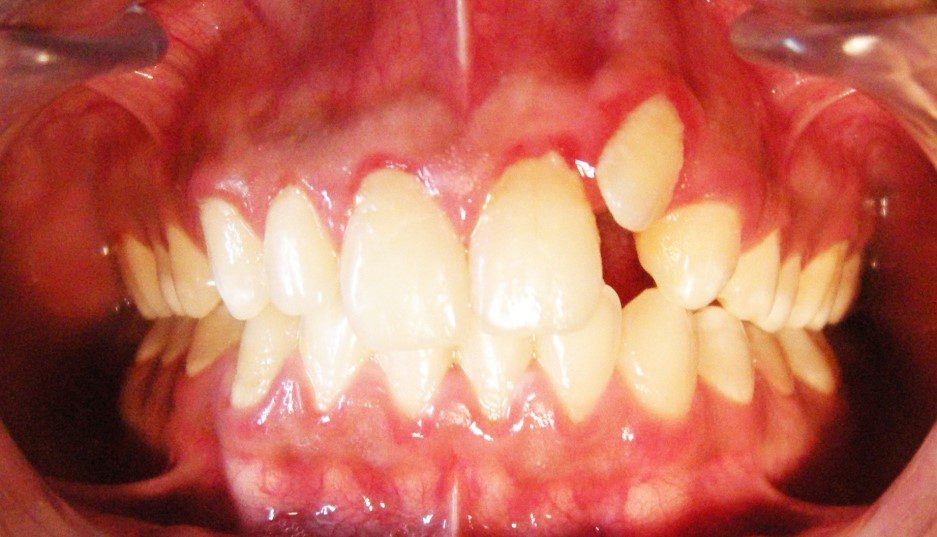

2. Cắn sâu

Trong trường hợp cắn sâu, mắc cài được gắn theo các quy tắc ngược lại với cắn hở. Trong hệ thống MBT răng có cắn sâu được gắn về phía rìa cắn thêm 0,5 mm.